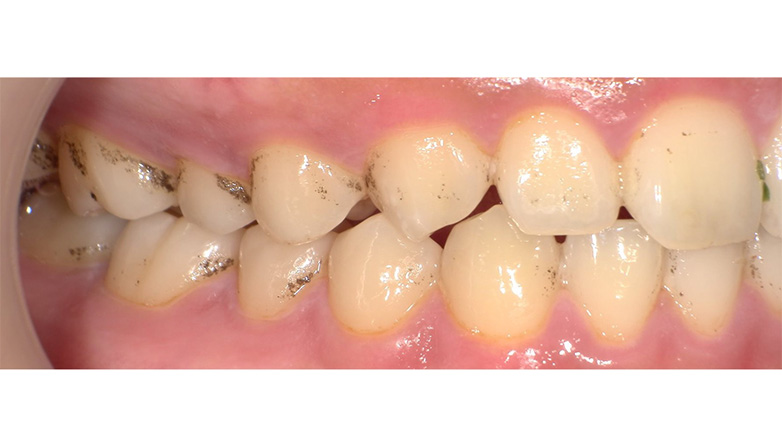

症例3

before

after

| 主 訴 | 着色を落としたい |

| 治療期間 | 通院 1回 |

| 治 療 費 | 1回 7,700〜11,000円(税込) |

| 治療内容 | PMTC |

| 治療のリスク | 歯自体の色を白くすることはできない。 しばらくすると再び着色することがある。 |